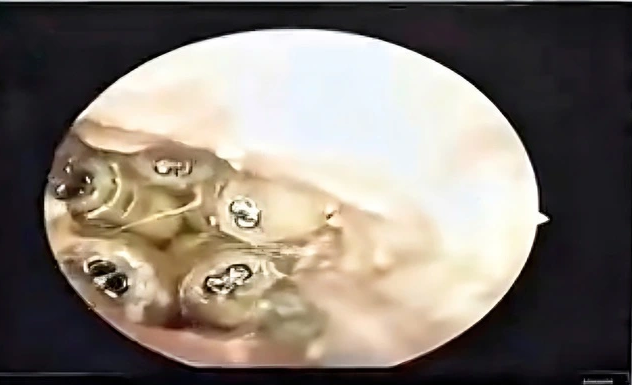

Old  Default Gắp 5 con giòi sống trong tai bệnh nhân

Các bác sĩ Khoa Tai mũi họng, Bệnh viện đa khoa Khánh Hòa vừa gắp 5 con giòi sống trong tai bệnh nhân 48 tuổi.

Sáng 25.10, một lãnh đạo Bệnh viện đa khoa Khánh Hòa cho biết, các bác sĩ Khoa Tai mũi họng vừa xử lý thành công một ca bệnh hiếm gặp khi phát hiện giòi sống trong tai bệnh nhân. Trường hợp này là lời cảnh báo về tầm quan trọng của việc vệ sinh tai, đặc biệt với người cao tuổi hoặc người không thể tự chăm sóc bản thân.

Trước đó, ngày 23.10, một nữ bệnh nhân 48 tuổi được người nhà đưa đến Bệnh viện đa khoa Khánh Hòa trong tình trạng tai sưng to, chảy dịch và đau dữ dội. Khi tiến hành soi tai, bác sĩ bất ngờ phát hiện nhiều vật thể màu trắng đang ngọ nguậy bên trong ống tai.

5 con giòi sống trong tai bệnh nhân

ẢNH: CẮT TỪ CLIP

Sau khi hút sạch dịch trong ống tai, các bác sĩ đã gắp ra 5 con giòi còn sống cùng xác một con côn trùng nằm sát màng nhĩ. Theo nhận định của bác sĩ, do bệnh nhân không thể tự chăm sóc bản thân, trong quá trình sinh hoạt có thể côn trùng đã chui vào tai, làm tổ và đẻ trứng, sau đó trứng nở thành giòi.

Đại diện Bệnh viện đa khoa Khánh Hòa cho biết, rất may trường hợp này được phát hiện kịp thời, nếu chậm trễ, bệnh nhân có thể bị thủng màng nhĩ, gây tổn thương nghiêm trọng đến thính lực. Đây là lời cảnh báo về việc cần chú trọng chăm sóc, vệ sinh tai mũi họng, đặc biệt với những người không thể tự vệ sinh cá nhân.

Các bác sĩ khuyến cáo, mọi người nên giữ tai luôn sạch sẽ, khô ráo và đến cơ sở y tế ngay khi có dấu hiệu đau, ngứa hoặc chảy dịch bất thường. Với trẻ nhỏ và những người không thể tự vệ sinh cá nhân, gia đình cần thường xuyên kiểm tra, vệ sinh tai để kịp thời phát hiện các dấu hiệu bất thường.